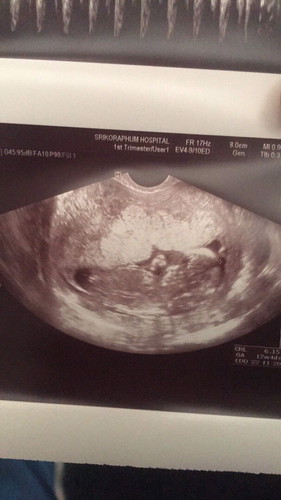

ท่าน้อง ท่านี้ ดูเพศไม่ได้ค่ะคุณแม่ และ 12w ยังเด็กไปที่จะทราบเพศนะคะ ต้องรอสัก 20w นะคะ^^

หมอบอกว่าไงบ้างคะ ถ้าดูจากในรูปน้อง12วีค ถูกต้องไหมคะ 12วีคยังระบุเพศไม่ได้หรอกค่ะ

สัก4-5เดือนค่อยซาวด์ดูเพศใหม่ก็ได้ค่ะแม่ มันจะชัวร์กว่านี้ 12วีคความยาวเค้า5-6 ซ.ม.เอง มันยังยากอยู่ค่ะ แต่ถ้าแม่ได้เจาะน้ำคร่ำหรือเจาะเลือดคัดกรองดาวน์ซินโดรม จะมีผลเพศอยู่ในนั้นด้วยนะคะ